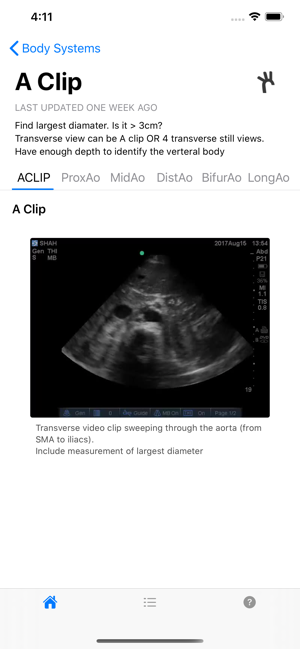

The premiere ultrasound app for minimal imaging criteria. Developed by the University of Miami Miller School of Medicine.

This application is only intended for educational and research purposes. Health care providers should use independent judgment when using this application for any purpose other than education and research. Non-medical personnel should seek a physician’s advice in addition to using this app and before making any medical decisions.